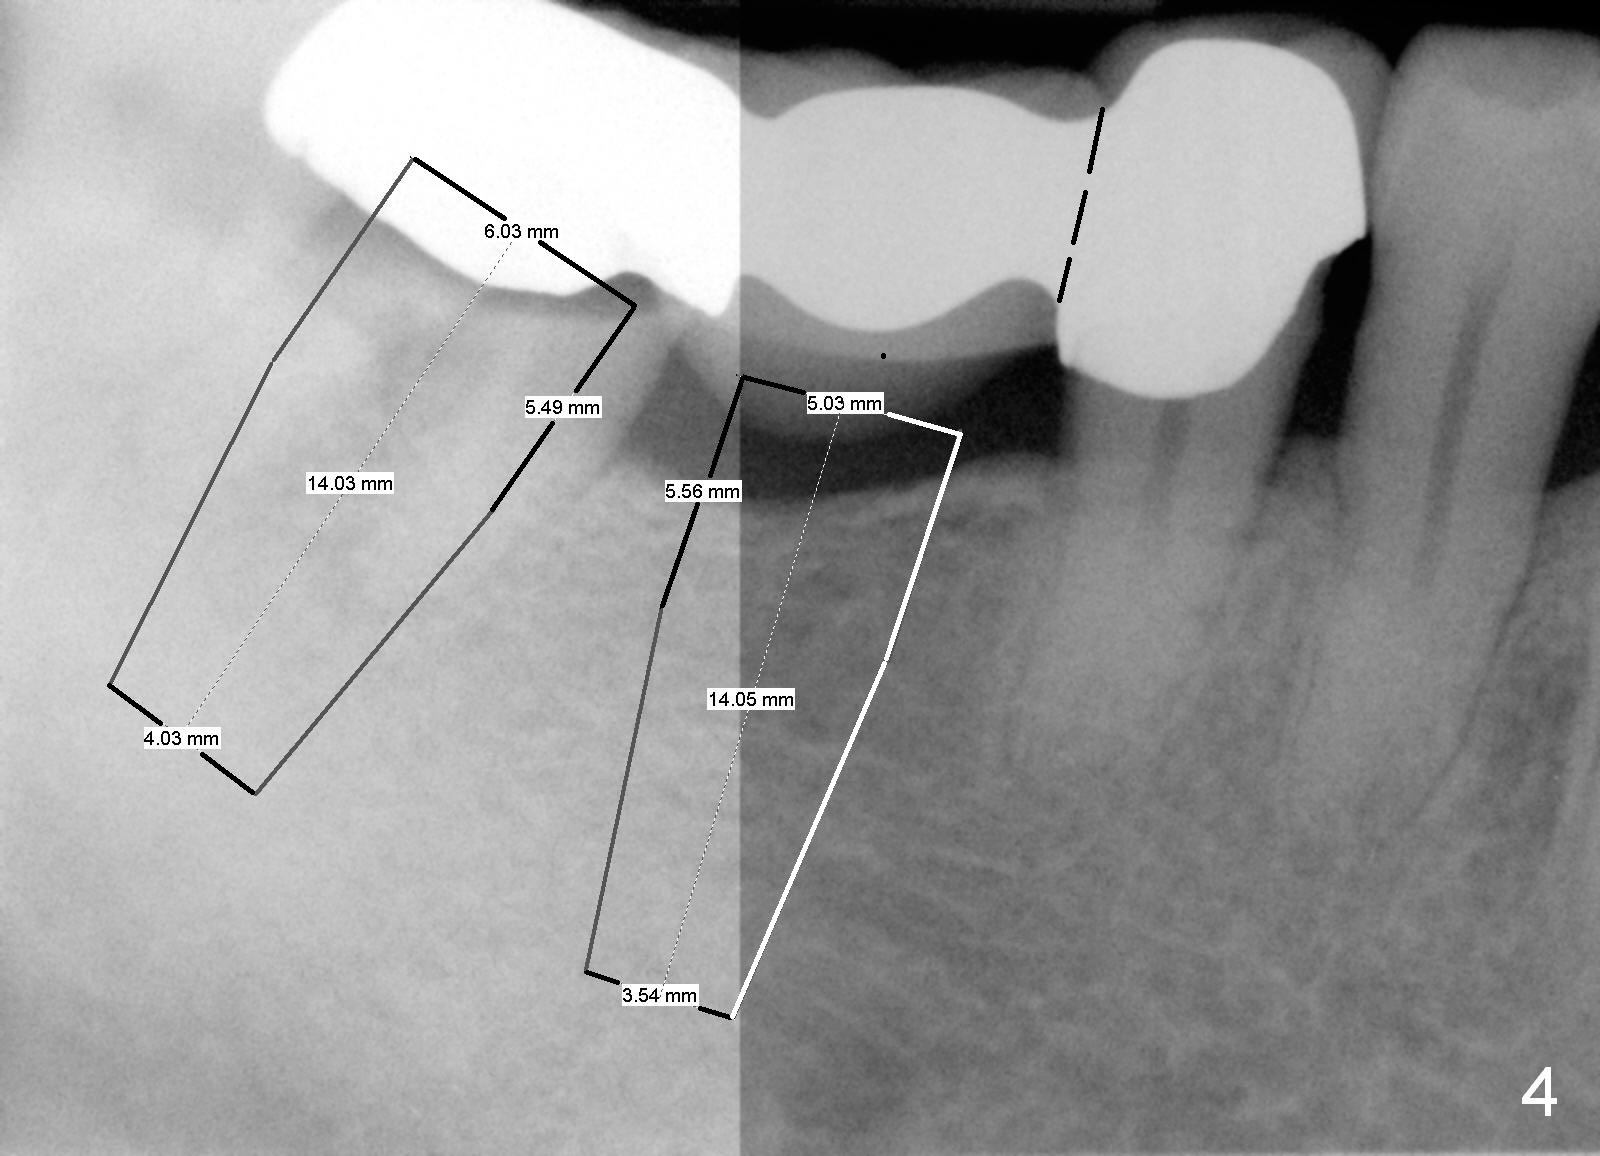

Before sectioning between #29 and 30 (Fig.4 dashed line), take Alginate impression for the lower right quadrant to fabricate a surgical stent. Two implants are to be placed at the sites of #30 (5x14 mm) and 31 (6x14 mm) (Fig.3,4).